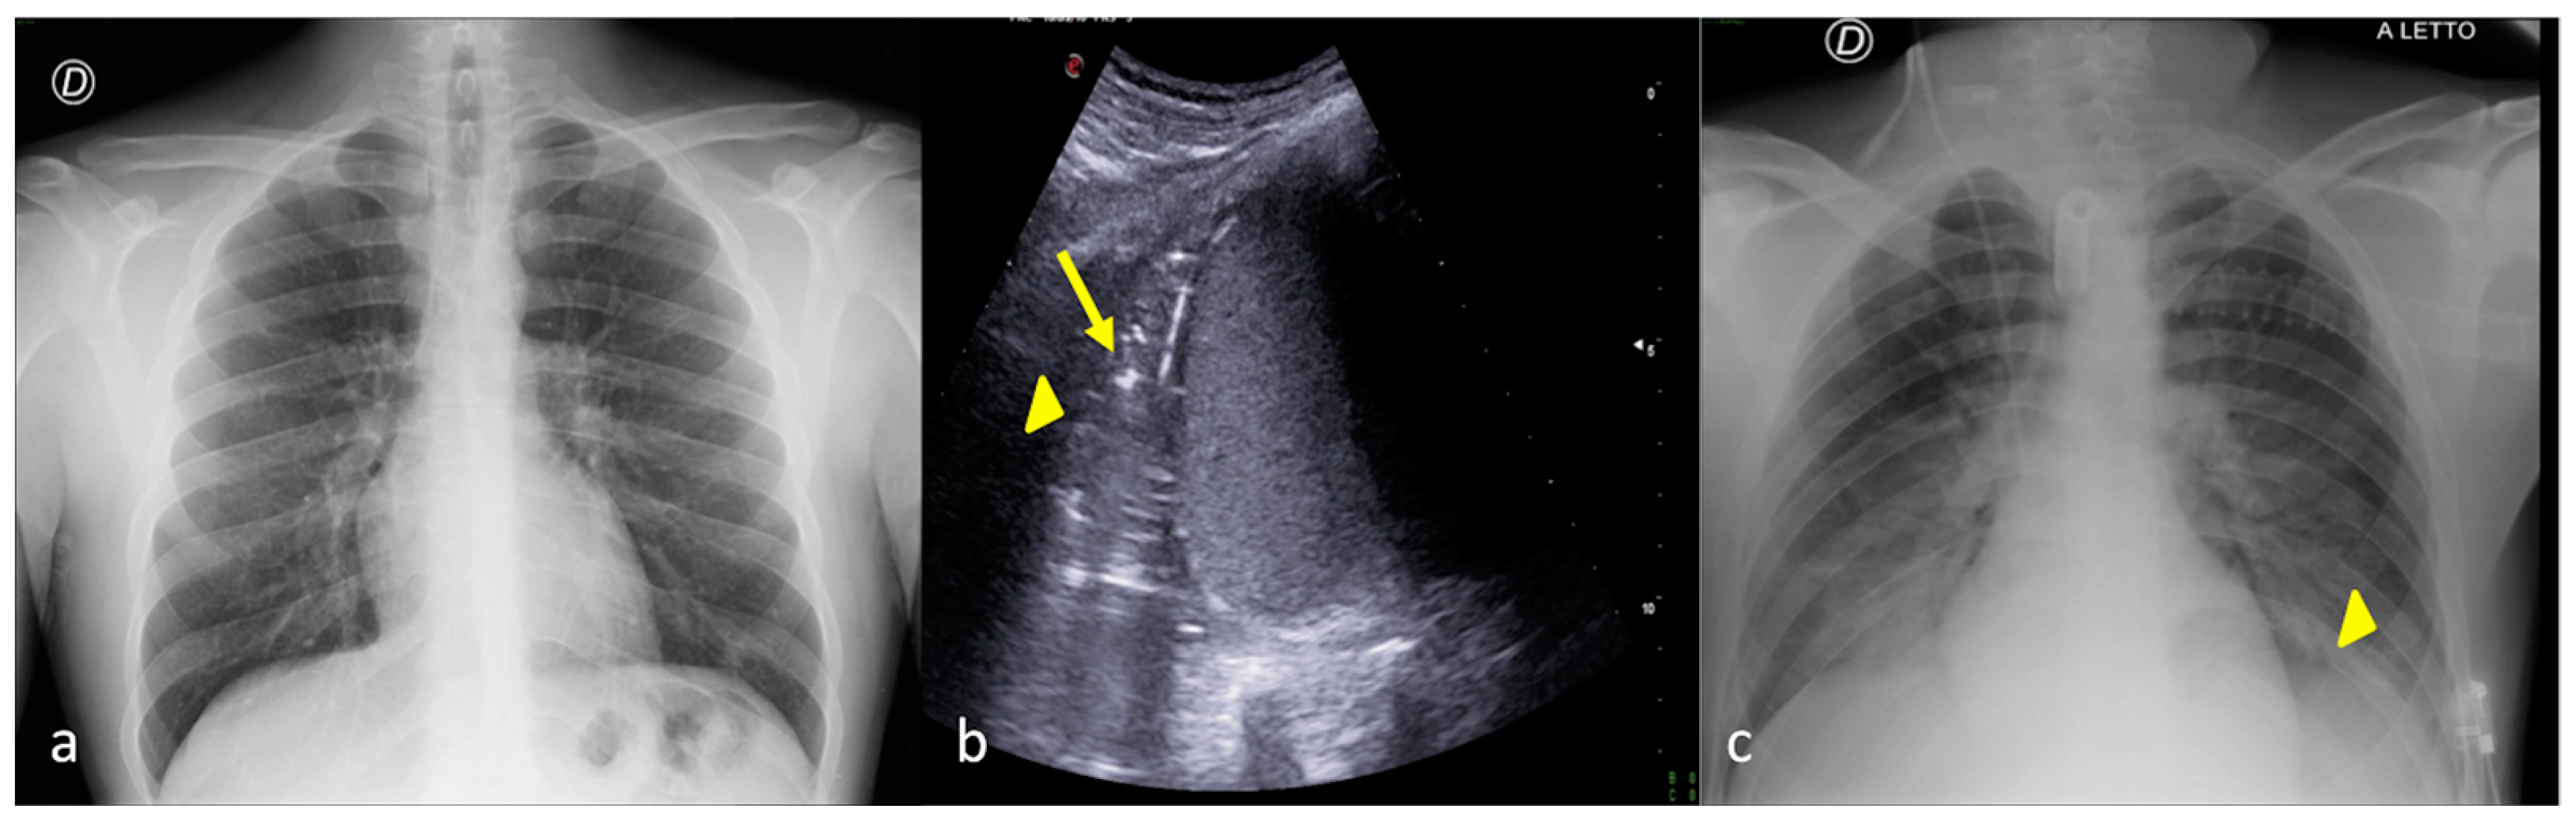

3. Confirming or Excluding Pneumothorax and Monitoring its Evolution

4. Checking and Monitoring the Devices